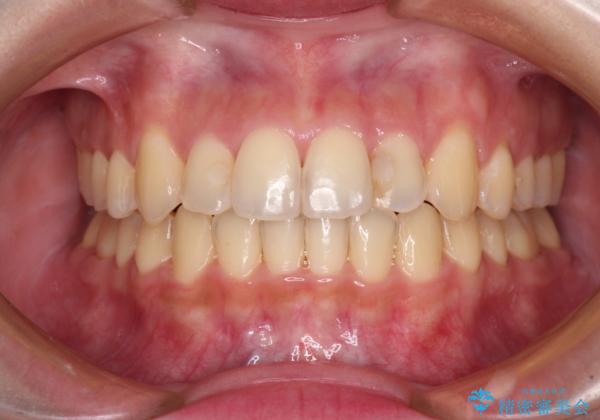

- 前歯のデコボコを気にして来院された患者様です。

上顎右側犬歯が八重歯になっており、それによって奥歯が前方に移動しているため、右側の咬み合わせの改善が必要と判断されました。

マウスピース矯正では改善に時間がかかる、あるいは改善しきれない可能性があることを伝えたところ、短期間で確実に治療ができるワイヤー矯正を選択されました。

より治療を速やかに行うため、上顎右側にアンカースクリューを使用し、目標としていた1年半ほどで治療を終えることができました。